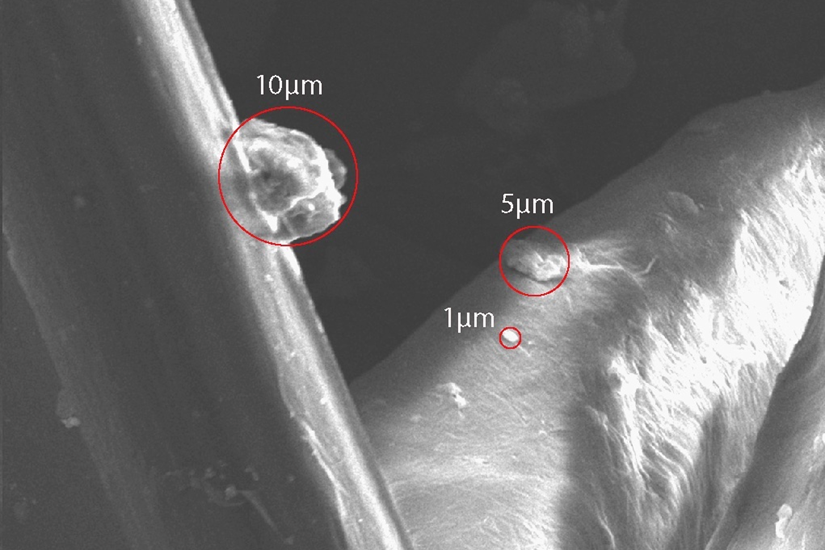

Ultrafine particles captured on Totobobo filter view under 2000X microscope

Credit: totobobo.com